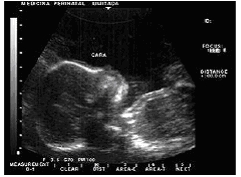

Uso del ultrasonido. Las ondas sonoras reflejadas por las diferentes partes del útero de una mujer preñada son distintas dependiendo del tejido con el que se encuentran.

El examen mediante ultrasonido tiene muchas aplicaciones durante el embarazo, permitiendo encontrar respuestas a toda una serie de dudas médicas. Algunas de las dudas más importantes que el ultrasonido es capaz de esclarecer son las siguientes: